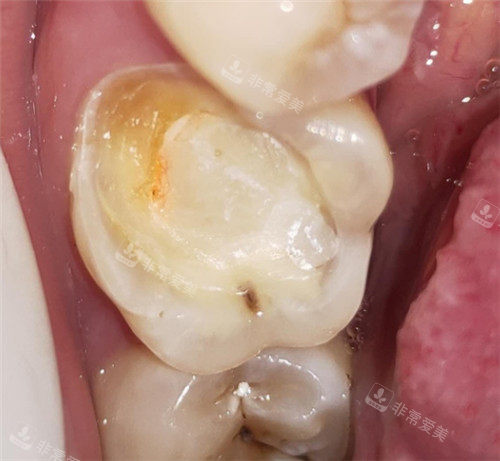

牙齿龋坏模型

牙齿龋坏清理图